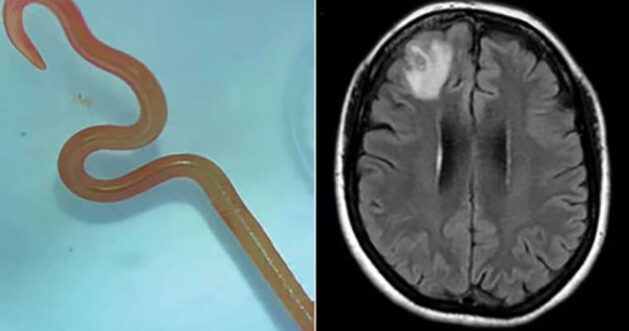

Avustralya’nın başkenti Canberra’da, bir kadının beyninden 8 cm uzunluğunda canlı solucan çıkarıldı. 64 yaşındaki kadın, 2021 yılında üç hafta süren karın ağrısı ve ishalin ardından sürekli kuru öksürük, ateş ve gece terlemeleri şikayetleriyle hastaneye yatırıldı. Şikayetlerine unutkanlık ve depresyon da eklenen kadına, MR taraması yapıldı. Canberra hastanesi infeksiyon hastalıkları doktoru Dr. Sanjaya Senanayake, normalde piton yılanlarında bulunan ve Latince adı “Ophidascaris robertsi” olan bir parazit olduğunu gördü.

Dr. Senanayake’nın meslektaşı Dr. Hari Priya Bandi, kadının beyninden solucanı çıkardığı operasyonu başarıyla gerçekleştirdi.

Dr. Senanayake ayrıca, vakanın dünyada “Ophidascaris robertsi” parazitinin insanlarda görüldüğü ilk vaka olduğunu vurguladı.